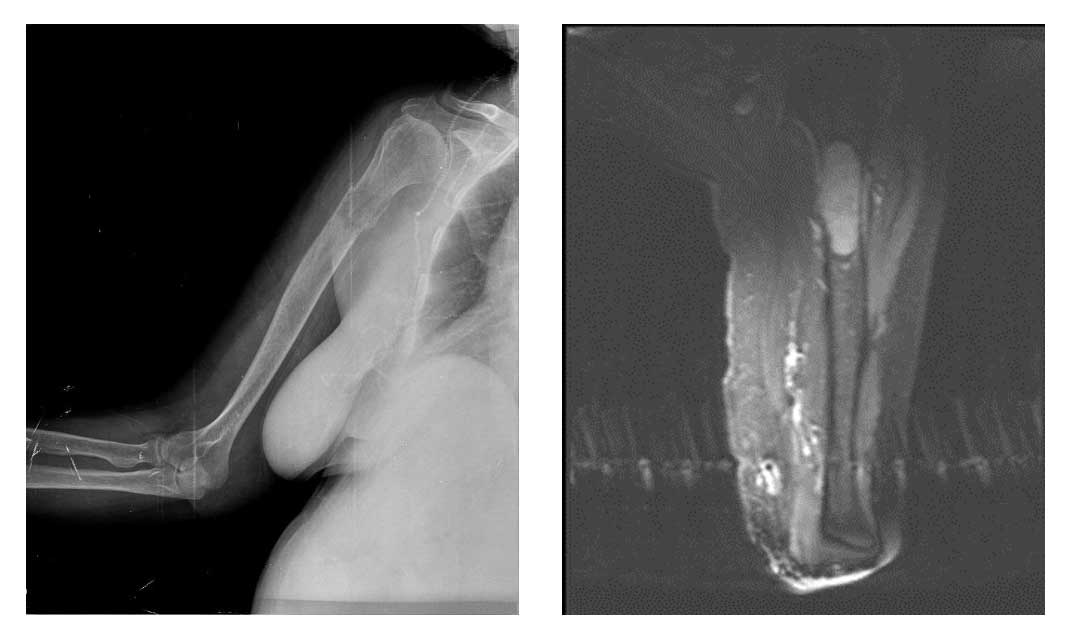

Ameliyat Öncesi: Röntgende humerus üst uçta harabiyet, MR’da o bölgeyi tamamen dolduran tümör dokusu görülmekte.